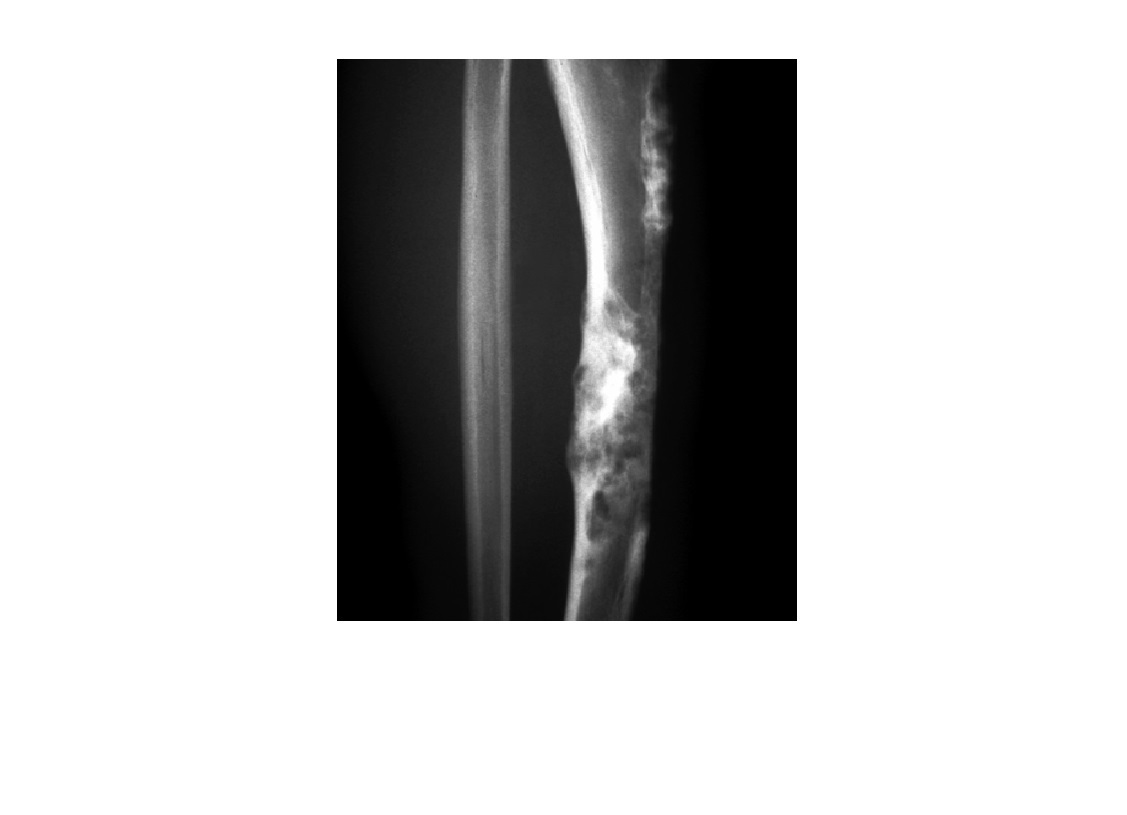

Adamantinoma

Low-grade, malignant lesion most frequently arising in tibial** cortex**

Mutlifocal

slcerotic and lytic compoents

*Cortically based lesion in anterior tibia